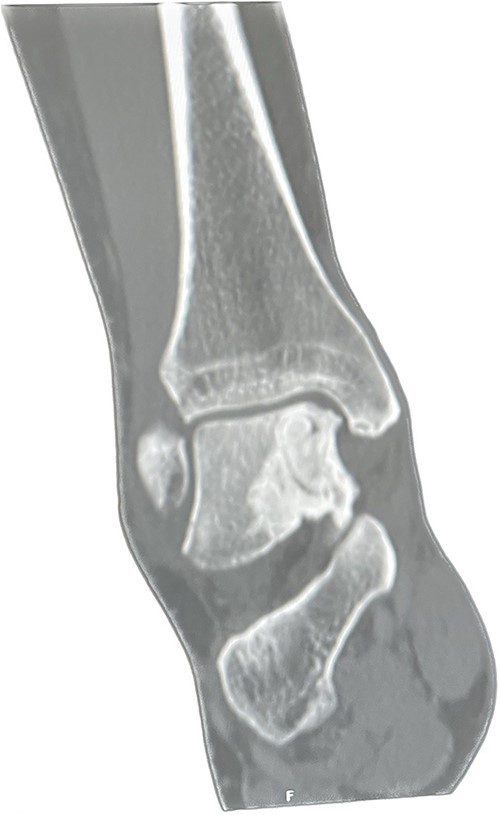

An X-ray of the ankle showed a radiolucency at the anteromedial aspect of the talus, suggesting a subchondral cyst. This lesion measured 18 × 18 × 11 mm on the CT scan in the medial patellar dome with a focal vacuum at the medial talocrural joint. The overlying cortex was thinned out with medial focal cortical defect. There was no collapse of the articular surface (Fig. 1).